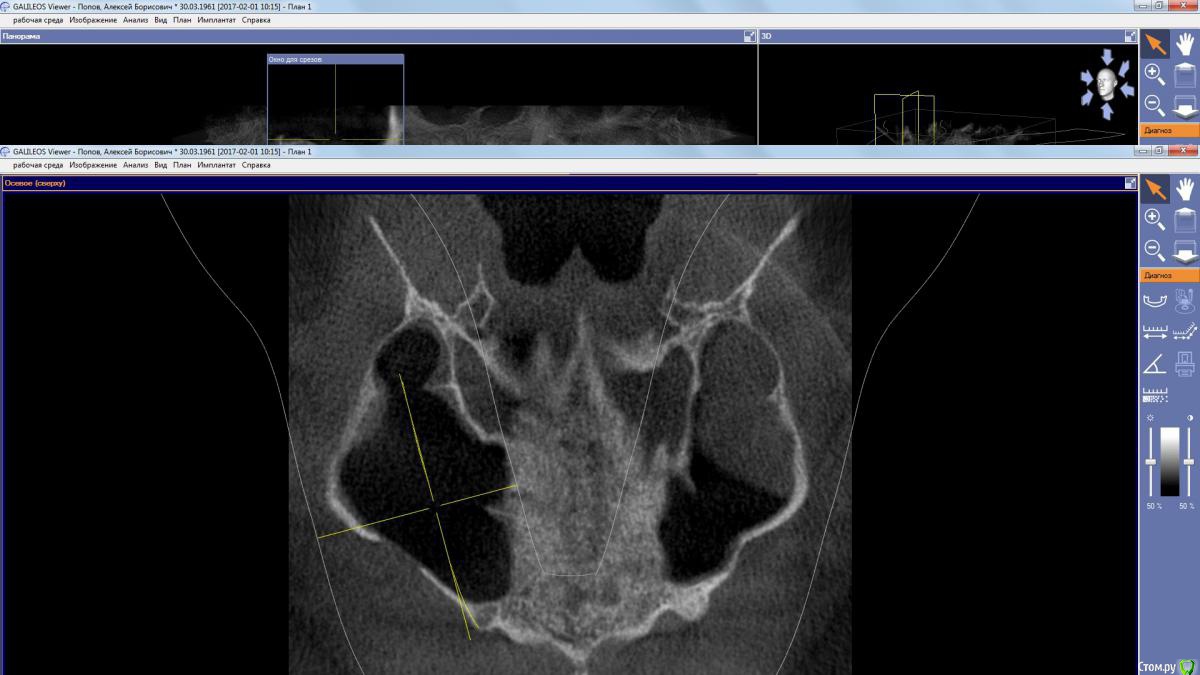

kamranchick Опубликовано 2 апреля, 2017 Поделиться Опубликовано 2 апреля, 2017 (изменено) Пациент обратился с целью восстановления жевания.удалял 16 зуб в поликлиннике, ему долбили, потом в ЧЛХ доставали что то).На кт вот такая ситуация, как посоветуете поступить? PS 1.7 и 1.8 зуб удалил. Изменено 2 апреля, 2017 пользователем kamranchick Ссылка на комментарий

kamranchick Опубликовано 2 апреля, 2017 Автор Поделиться Опубликовано 2 апреля, 2017 Да дыры какие то и на окклюзионной поверхности и сбоку) это и отпугнуло Ссылка на комментарий